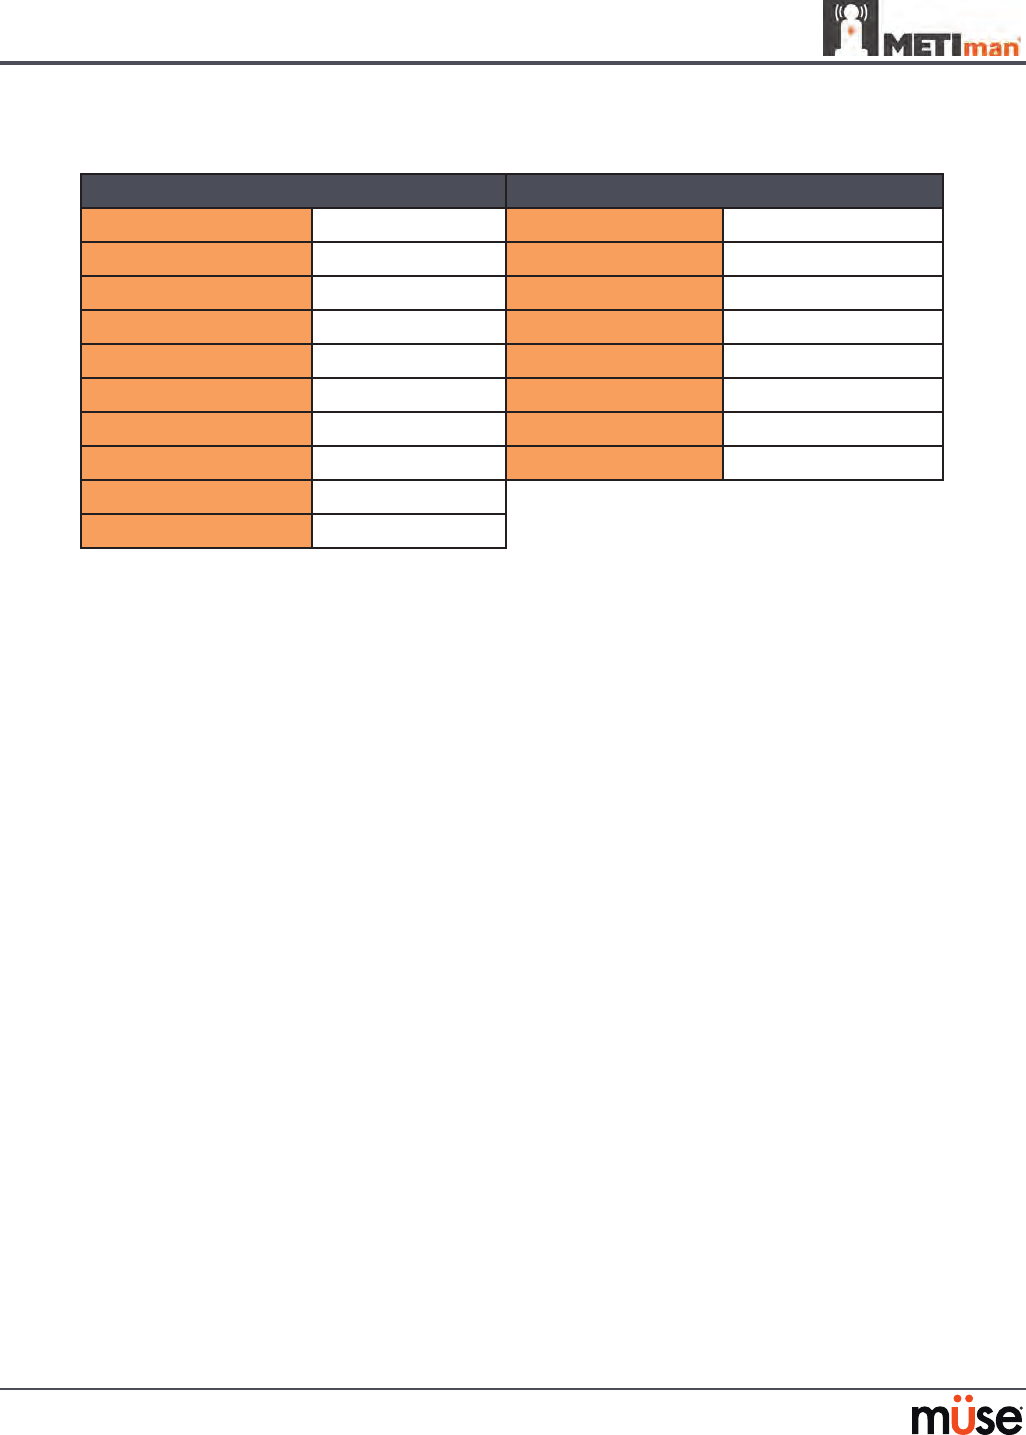

Cardiovascular System

Anatomy,

Physiology and

Clinical Signs

Clinical Interventions, Patient Monitoring

and Scenarios.

Software Control

Manual

Control

Heart Sounds Normal and abnormal heart sounds are

synchronized to the cardiac cycle and audible

to a standard stethoscope. Heart sounds can be

auscultated over the left and right upper sternal

border, right lower sternal border and apex.

None required;

specic sounds can be

selected.

VIEW:

Cardiovascular

None required.

5-Lead ECG ECG waveforms can be viewed on a standard

monitor and/or on the TouchPro Patient monitor.

Normal and abnormal cardiac rhythms are

linked to patient physiology (e.g. blood pressure,

cardiac output).

None required;

specic rhythms can

be selected.

ECG monitor may

be utilized.

Myocardial

Ischemia

Myocardial oxygen supply and demand

automatically inuence the cardiac rhythm,

yielding response to hypoxemia.

None required, but

adjustable.

None required.

Palpable Pulses Carotid, brachial, radial, femoral, popliteal,

posterior tibial and dorsalis pedis pulses can be

palpated bilaterally and are synchronous with

the cardiac cycle. A pulse decit automatically

occurs if the systolic arterial blood pressure falls

below specied thresholds.

None required, but

adjustable.

VIEW:

Available on

all views on the Run

screen

None required.

Non-Invasive

Blood Pressure

Measurement

Systemic blood pressure can be measured using

the return-to-ow technique. Korotko sounds

can also be auscultated.

None required. Use of modied

blood pressure

cu.

145

Realistic Cardiovascular Interventions

Anatomy,

Physiology and

Clinical Signs

Clinical Interventions, Patient

Monitoring and Scenarios.

Software Control

Manual

Control

Chest

Compression

Eective chest compression results in articial

circulation, cardiac output, central and

peripheral blood pressures, palpable pulses, and

CO2 return.

None required, but

adjustable.

None required.

Cardiac

Monitoring

The desired arrhythmia can be selected. The response to

clinical intervention

must be controlled by

the instructor.

VIEW:

Cardiovascular

None required.

Debrillation METIman supports operation with a variety of

manual and automatic external debrillators.

Debrillation can

be simulated by the

instructor under the

Interventions palette

VIEW:

Cardiovascular

See Debrillation

below for

debrillation disk

locations and

instructions.

Cardiac Pacing Transthoracic cardiac pacemaker can be used

with METIman. Pacing results in appropriate

physiological changes in blood pressure and

cardiac output.

None required. See Pacing below

for cardiac pacing

disk locations and

instructions.

154